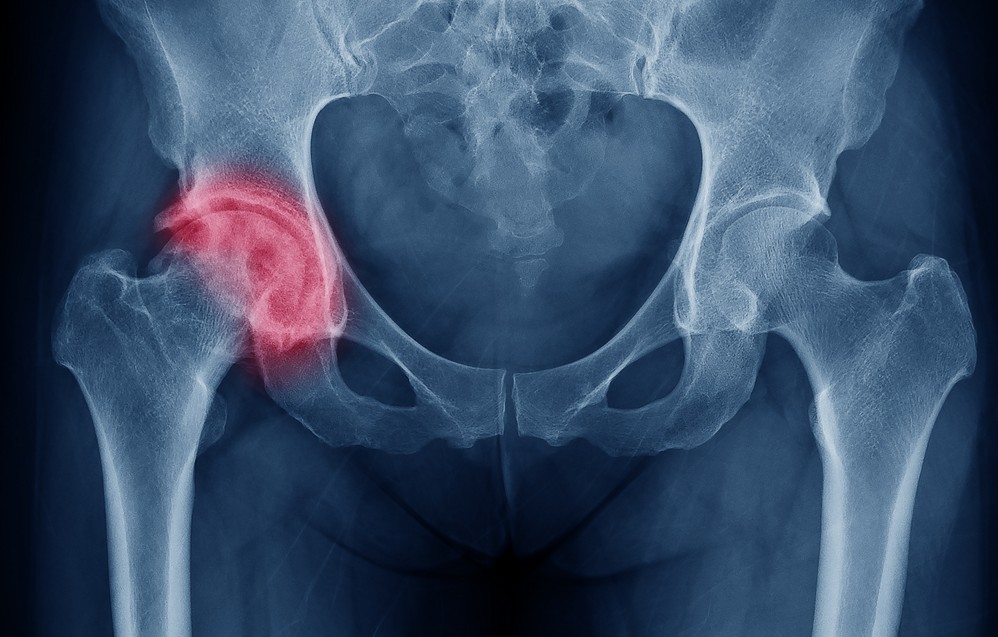

Шейка бедра – узкий участок между головкой бедренной кости и её телом, являющийся важным звеном в опорно-двигательном аппарате. С возрастом структура костной ткани становится более пористой, кровоснабжение ухудшается. Нагрузка на тазовые кости остаётся высокой, что усугубляется при лишнем весе. Из-за этих факторов шейка бедра становится хрупкой даже при незначительных травмах – падении с кровати или при неосторожном шаге.

Точный диагноз ставится с помощью рентгена, КТ или МРТ. Чем раньше выявлена травма, тем выше шансы на успешное восстановление после перелома шейки бедра.